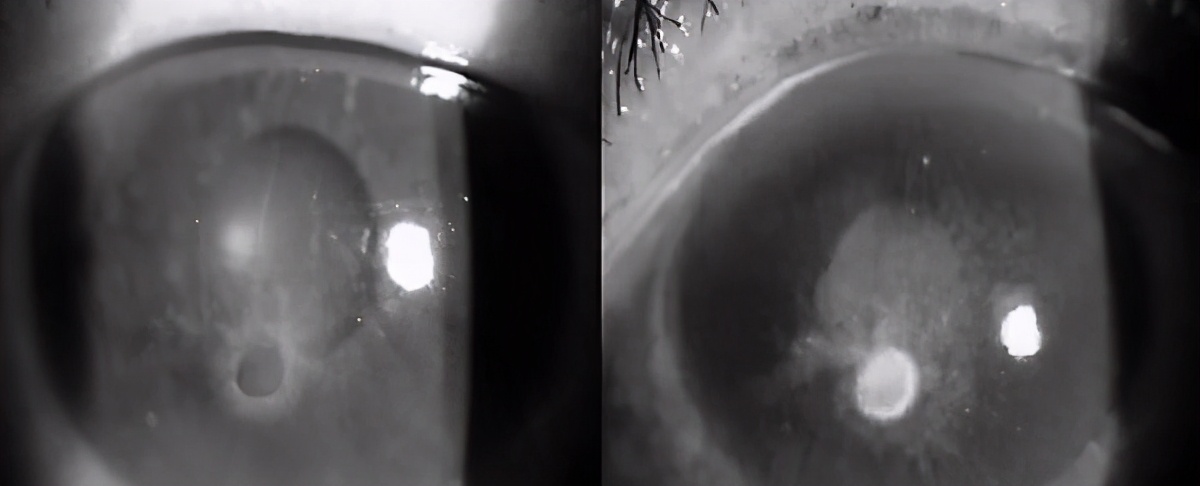

日前,有一张照片引起了很多人议论:

眼科医生在朋友圈里贴图,说他们接诊了一位年轻女性,眼角膜损坏得不成样子,视力严重下降,新生的血管已经长到了角膜里,甚至达到了瞳孔边缘。